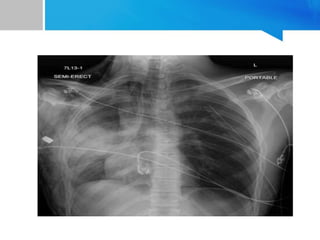

Tension pneumothorax • Etiology-usually traumatic • Pathophysiology Parenchymal tear in lungs act as a one way valve With each inhalation additional air is accumulated without any means of escape Leads to increased intrathoracic pressure with mediastinal content shift to contralateral chest causing decrease in venous return

Manifest as dyspnea,tachypnea,chestpain,hypoxia,diminished/absent breathe sound